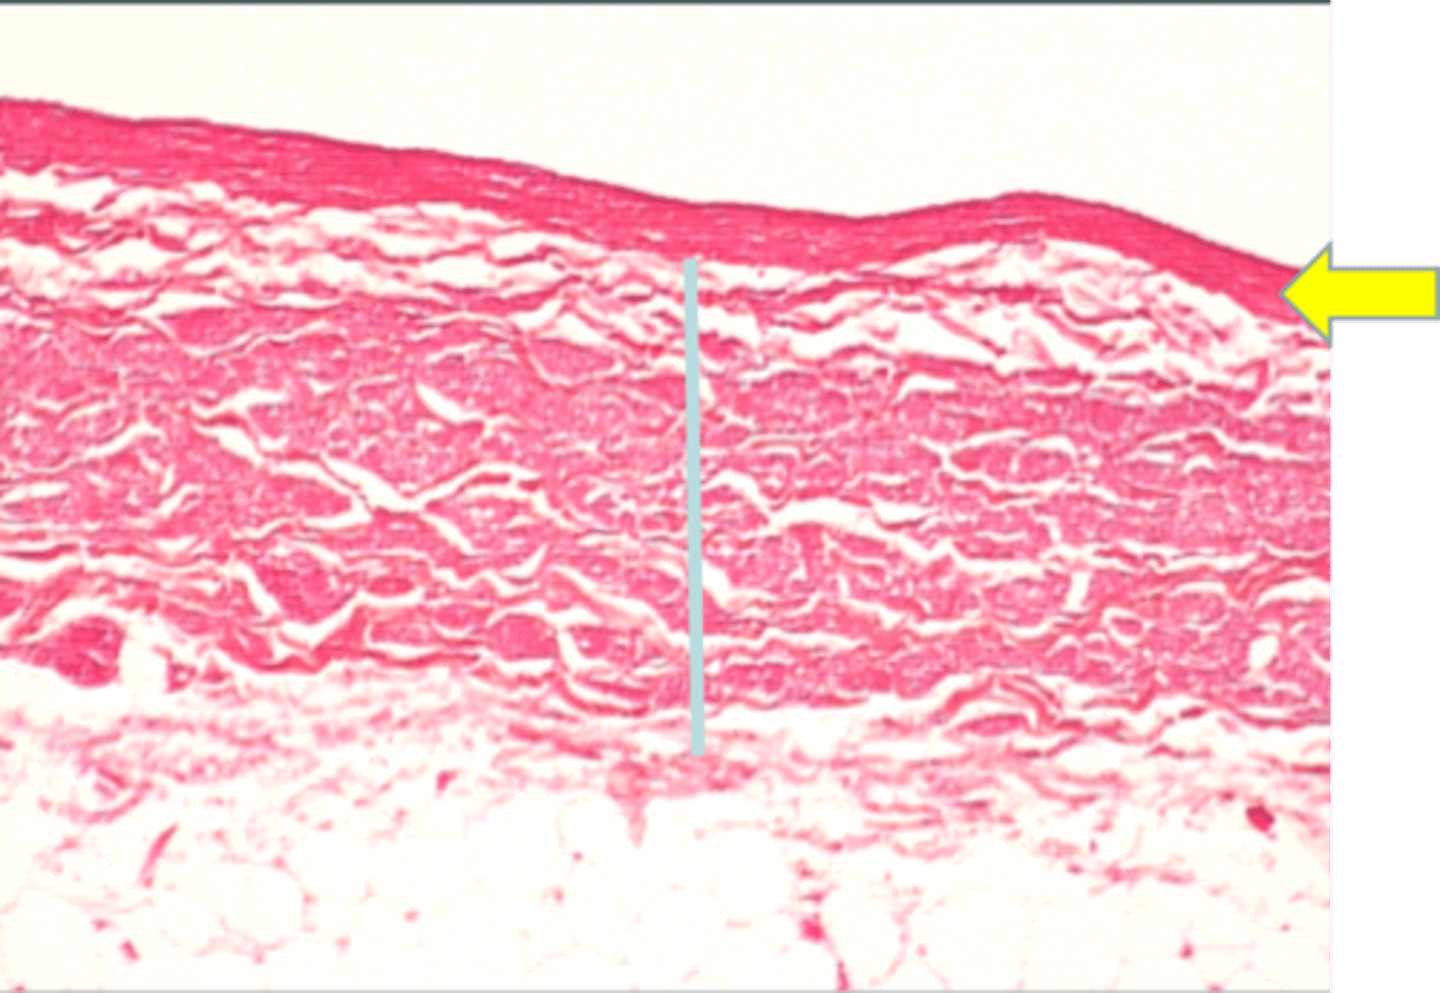

aorta

elastic, large, artery with vasovasorum

AKA conducting artery

tissue

tunica media of large vein

yellow arrow

tunica adventitia of large vein

blue line

large vein

ID tissue